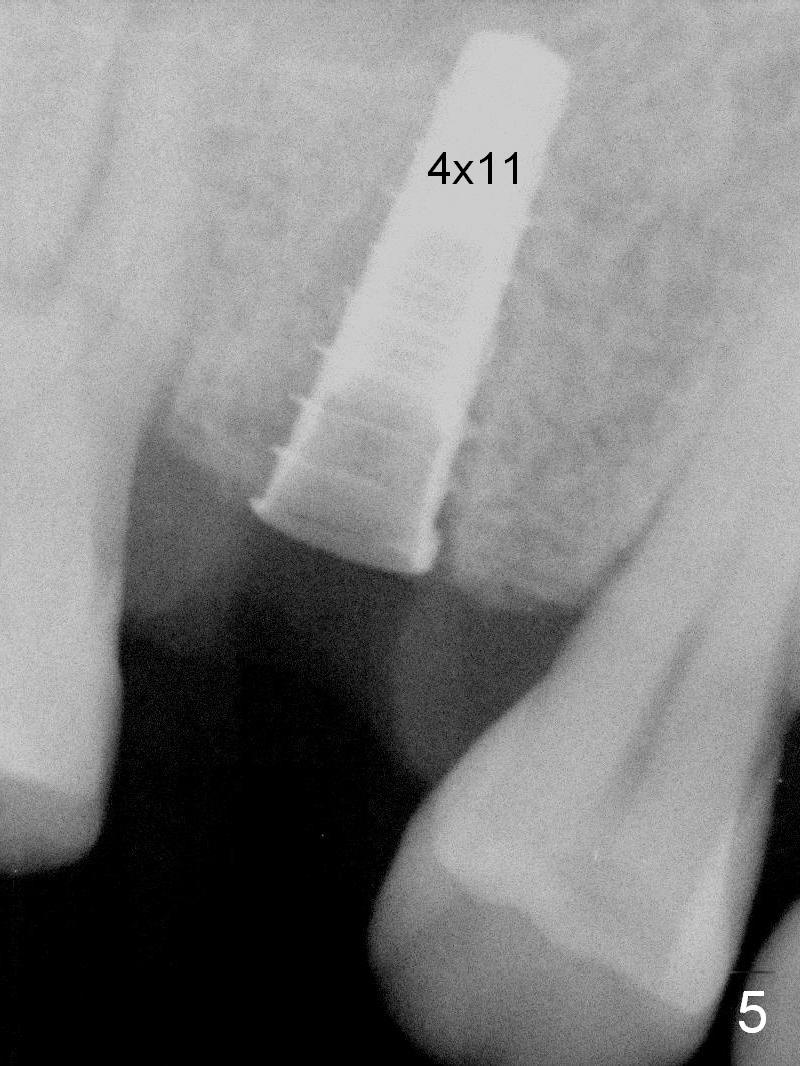

A 47-year-old man returns emergently with subgingival fracture of the lingual (L) cusp of the tooth #4 (Fig.1-3).  After extraction (no bony defect) without drilling, a 4x11 mm dummy implant is placed as a tap drill with satisfactory stability (Fig.4,5).  To get subcrestal placement, a shorter (4x9 mm) implant is inserted with insertion torque of < 35 Ncm.  In retrospect, a larger implant (4.5 mm) would be better in term of primary stability.  After allograft placement into the buccal and lingual gaps, a 4.5x4(4) mm abutment is placed for an immediate provisional.  There is a peri-implant gap 7 months postop (Fig.7<, as compared to the implant at #2 (6 months postop)) .  When the loose abutment is being retightened, the patient feels pain, although the gingiva appears healthy (Fig.8).  A larger implant should have been used; the abutment should have been removed.  The implant dislodges while the abutment is untightened 8 months postop.  The osteotomy is found intact.  A 4.5x11 mm dummy implant is placed 2 mm subgingival with 20 Ncm (Fig.9).  When a 4.5x11 mm definitive implant is placed 3 mm subgingival (Fig.10,11), torque reaches 50 Ncm.  A 5.5x3 mm healing abutment is placed.  Three months postop, the implant is stable (Fig.12,13) and impression is taken.